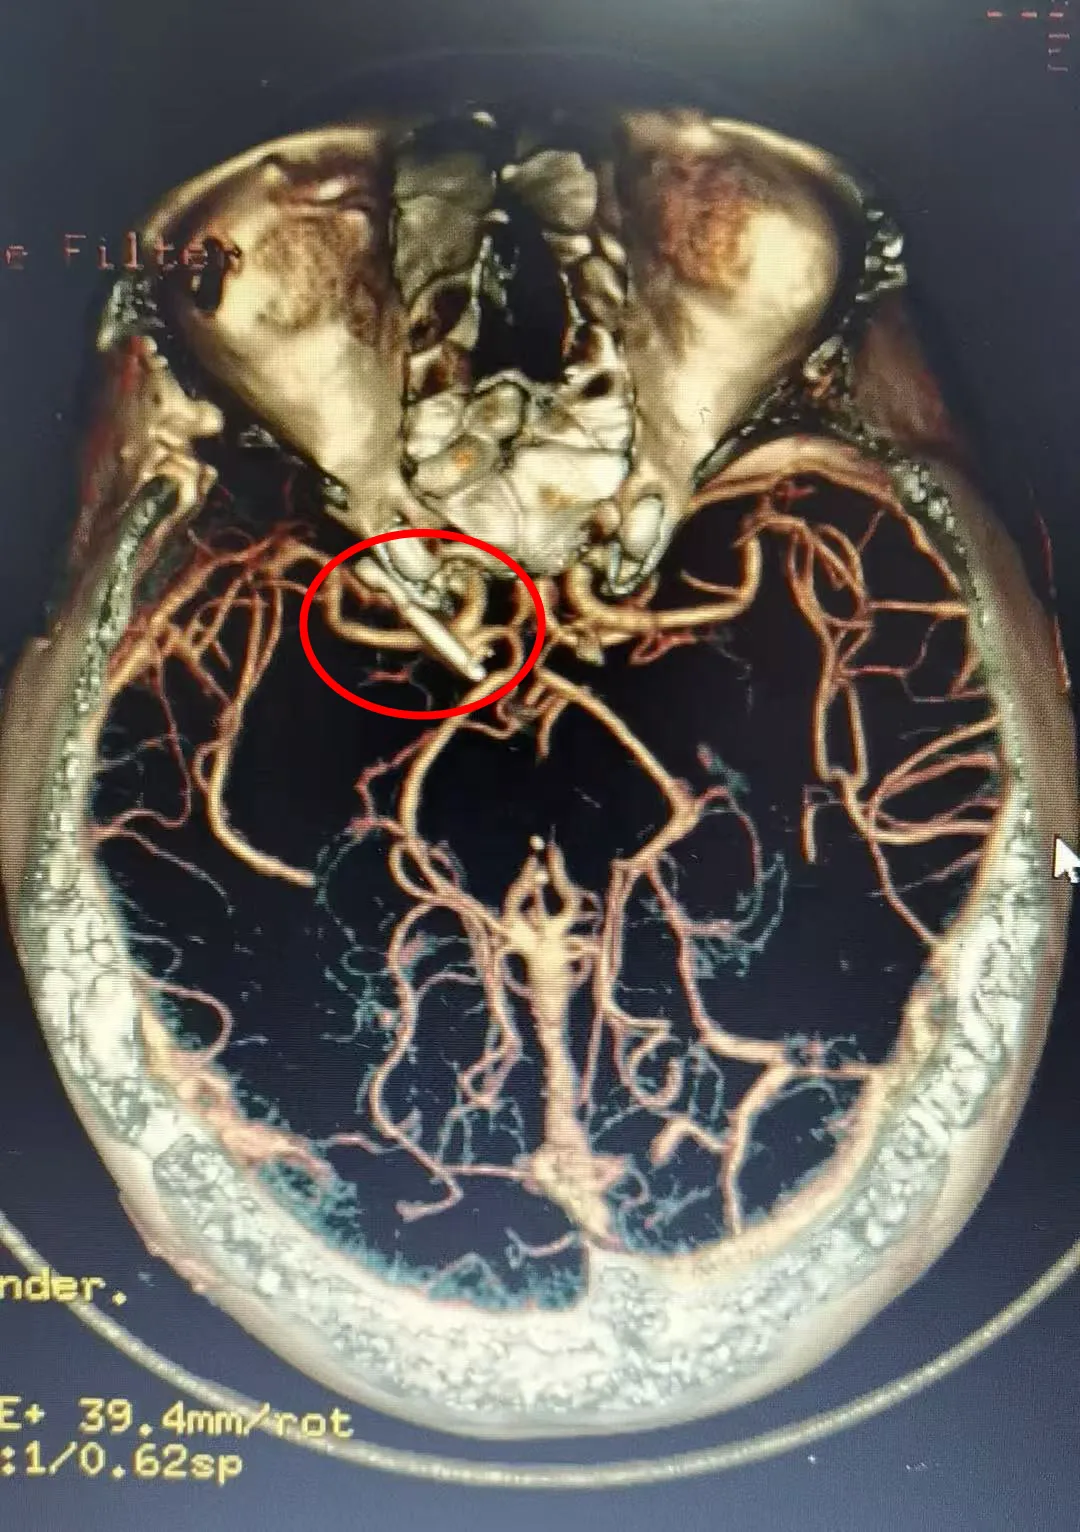

术后头部CTA

手术在湘雅医院神经外科教授的指导下,由神经外科副主任罗永兴主任医师主刀,龙春副主任医师担任助手,在麻醉科和手术室的配合下,为患者实施了显微镜下颅内动脉瘤开颅夹闭术,手术非常顺利。术后,予积极消炎、化痰、腰穿、护胃、营养支持、抗癫痫、预防血栓等对症治疗后,患者病愈出院。